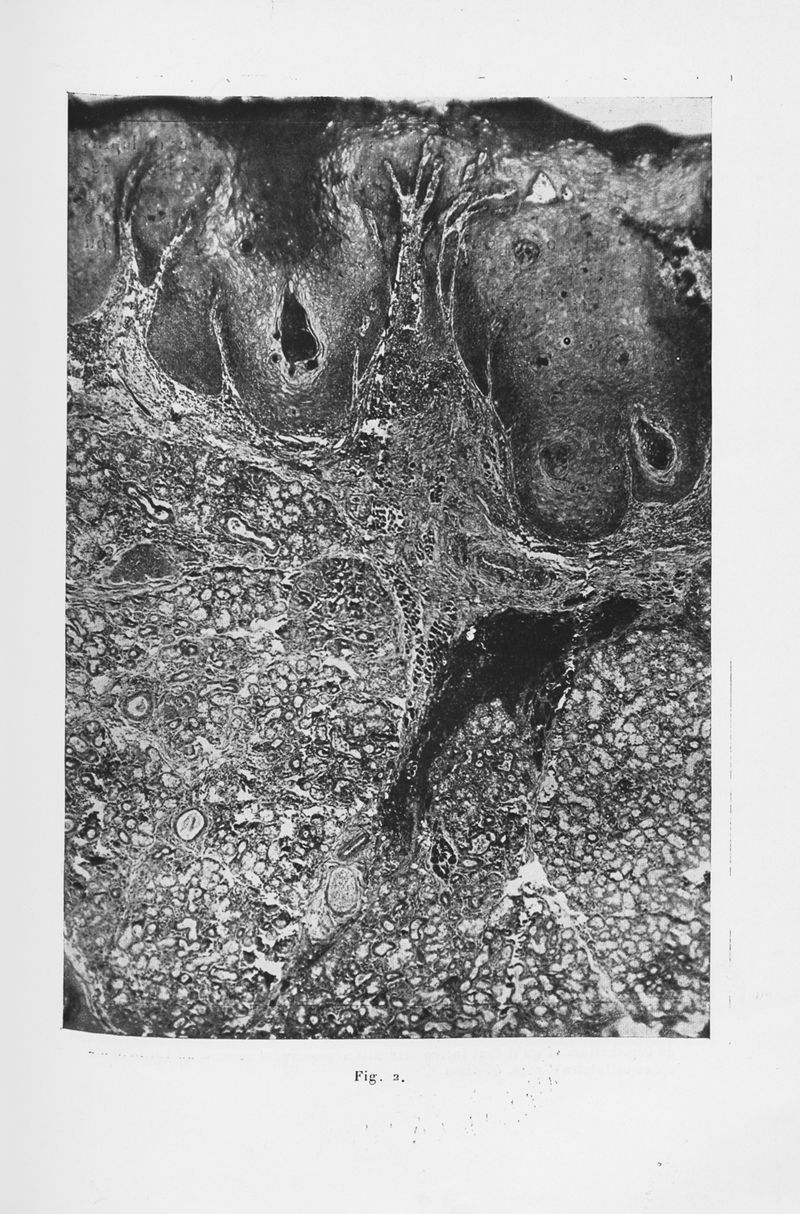

Annales de dermatologie et de syphiligraphie

7ème série, tome VI. - Paris : Masson, 1935.